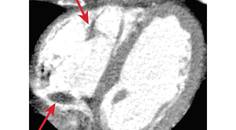

Interventional Neuromuscular Ultrasound

John Norbury, MD; Michael S. Cartwright, MD, MSJohn Norbury, MD; Michael S. Cartwright, MD, MS